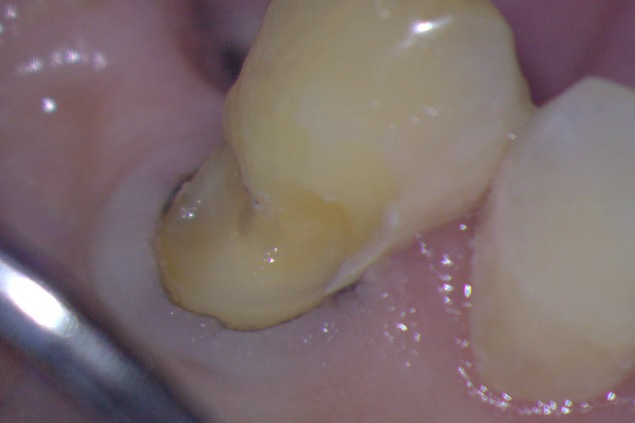

Following caries removal and toileting of the preparation (Figures 1 and 2), the ACTIVA BioACTIVE-BASE/LINER is placed directly over the deepest dentinal areas in increments of 2mm (Figure 3). Each layer is subsequently light cured.